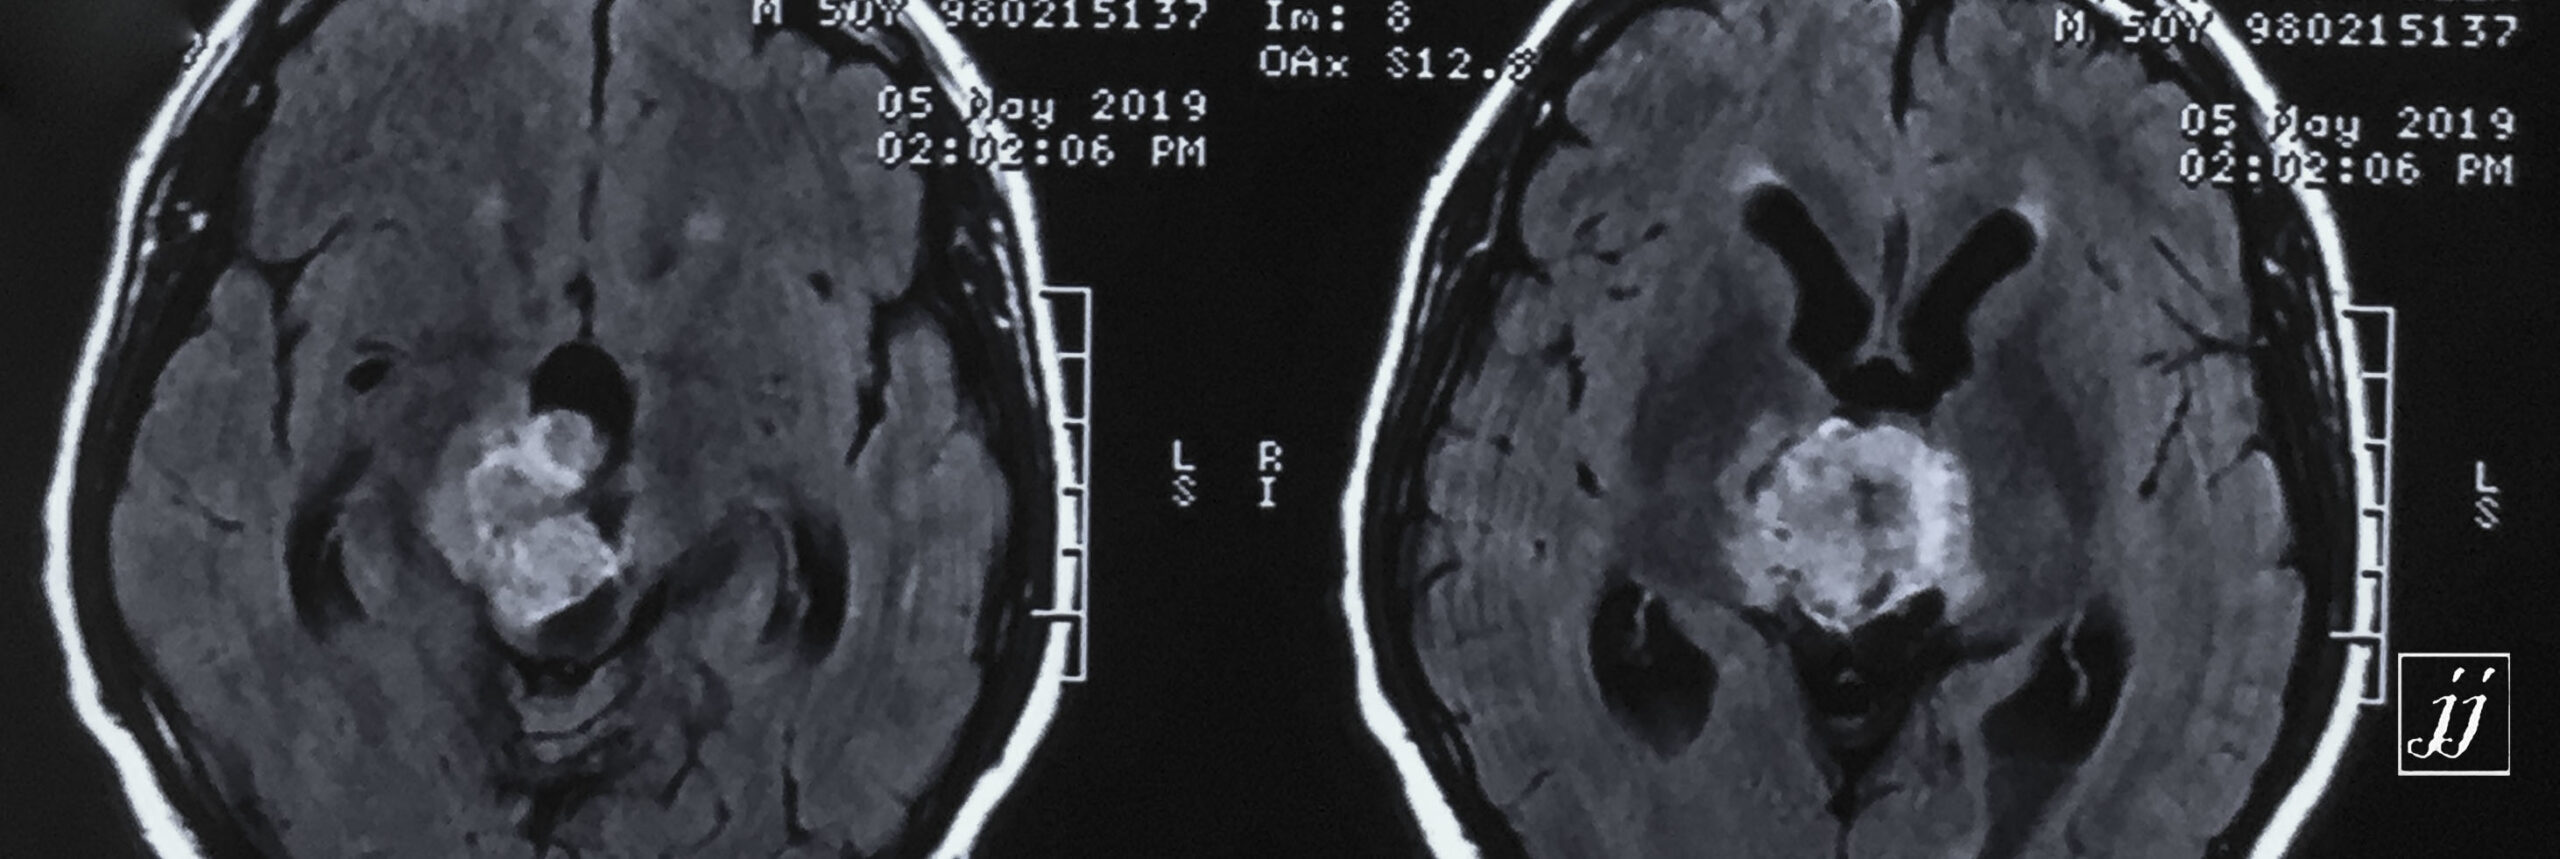

Brain- hugged size tectal and quadrigeminal meningioma (3)